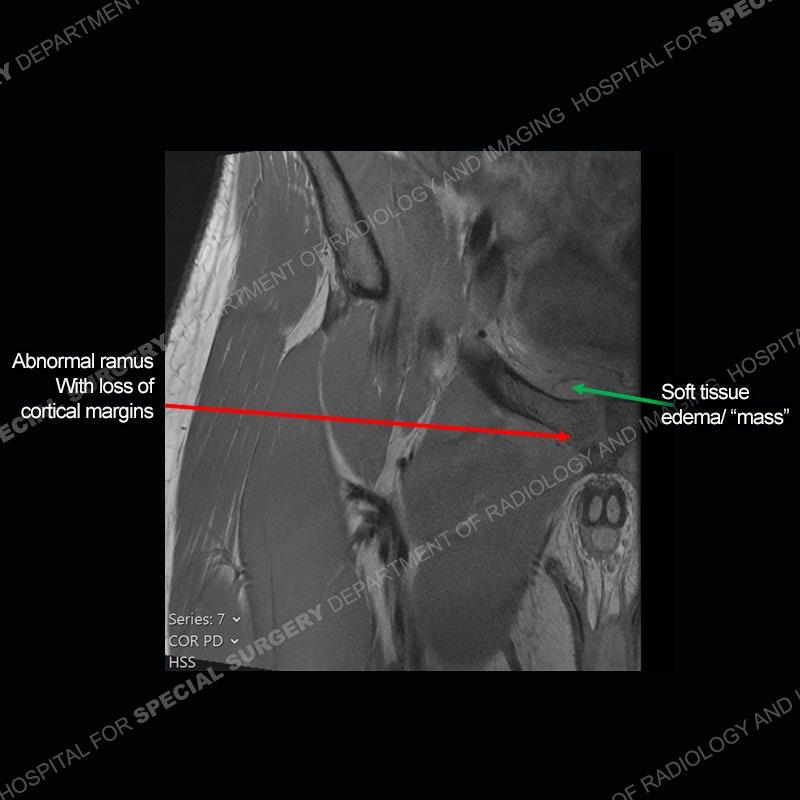

Radiographs did not demonstrate any clear abnormality. The MRI shows markedly abnormal signal of the right superior pubic ramus and abnormal signal/”mass” extending into the adjacent soft tissue. The inferior articular surface of the ramus showed what was thought to be bony destruction. CT examination shows a destructive process of the right superior pubic ramus.

Subsequent MRI in a very short time interval shows markedly increased abnormality of the ramus and increased edema and “mass” of the soft tissue. Post contrast imaging shows multiple, rim enhancing collections of the soft tissue and similar albeit less conspicuous enhancing collection of the ramus.